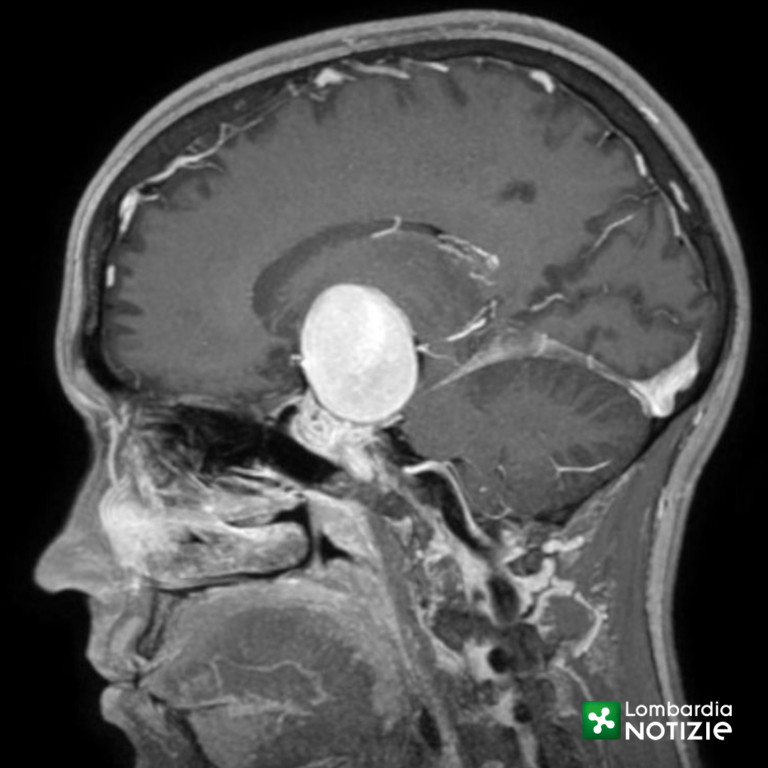

Aneurisma di 4 cm dell’arteria carotide interna al cervello

“L’aneurisma cerebrale è una patologia acquisita nella quale la parete di un arteria cerebrale si sfianca e forma un «palloncino» che rischia di esplodere. In questo caso si trattava di un rigonfiamento dell’arteria carotide interna del diametro di ben 4 cm (gli aneurismi vengono definiti «giganti» sopra i 2,5 cm)” – spiega Marco Cenzato, Direttore della Neurochirurgia. “Spesso gli aneurismi rimangono silenti oppure vengono riscontrati in maniera accidentale durante esami diagnostici per altre problematiche. Quando si manifestano è perché stanno diventando instabili e il rischio di rottura è altissimo, con esito, purtroppo, spesso letale”.